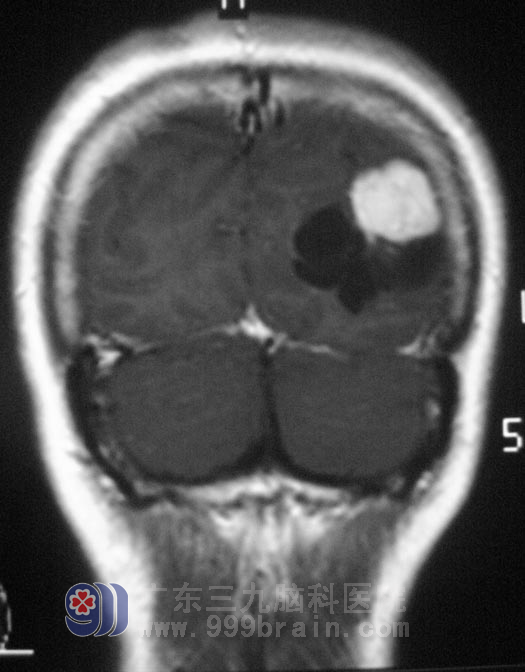

广东三九脑科医院MR提示:左侧顶枕叶占位,性质待排。综合神经外科 鲁明主任告诉温女士,肿瘤不是摔跤摔出来的,这次摔跤后检查偶然发现,也算是因祸得福,肿瘤就应该是早发现,早治疗。

9月19日,由鲁明主任主刀,在全麻下行左侧顶枕部占位切除术,术中见肿瘤表面淡黄色,质软,血供一般,在显微镜下电凝完整切除肿瘤。术后病理为:(左顶枕叶)节细胞胶质瘤,WHO I级。经过进一步的治疗,温女士康复出院。

▲手术前